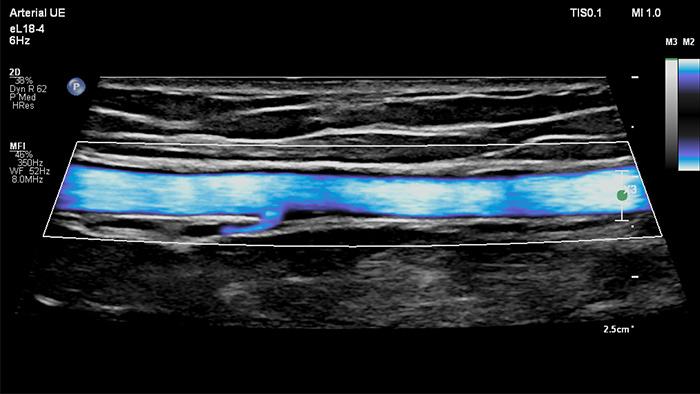

Philips MicroFlow Imaging wurde für die Erkennung langsamer und schwacher Blutflüsse in Gewebe entwickelt und verbessert bei Gefäßuntersuchungen die Flussauflösung mit beeindruckender Empfindlichkeit. Subtile, pathologische Strömungsverhältnisse um stenotische Plaques lassen sich durch die hohe Auflösung und minimale Artefakte visualisieren und charakterisieren, was die Diagnosesicherheit unterstützt.